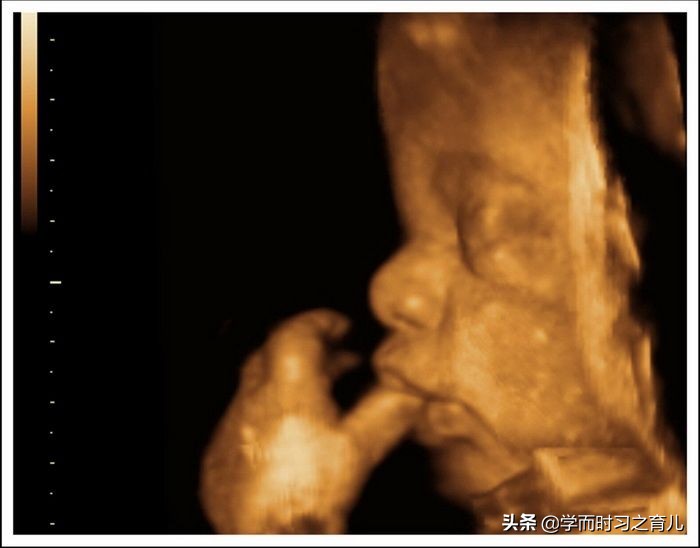

其实一般在怀孕22~26周,医生会安排准妈妈进行胎儿大排畸检查,主要通过三维或者四维彩超(两者选择其中一个即可)进行,可以说这是整个孕期最重要的检查项目之一。

虽然四维彩超已经是目前最先进的技术了,不仅可以检查胎儿的发育情况,还可以实时看到胎宝宝的各种动作,但这还是无法检查出胎儿所有的畸形,存在一定的局限性。